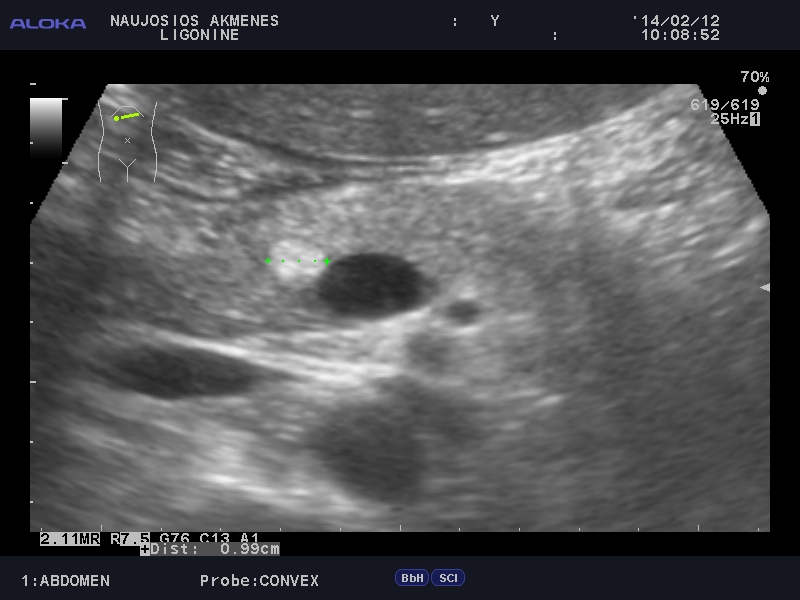

Очаг в панкреас

Мужчина средних лет. Жалоб нет.

qqqq_20140212_ABDOMEN_0011.JPG

Рекомендовал КТ.